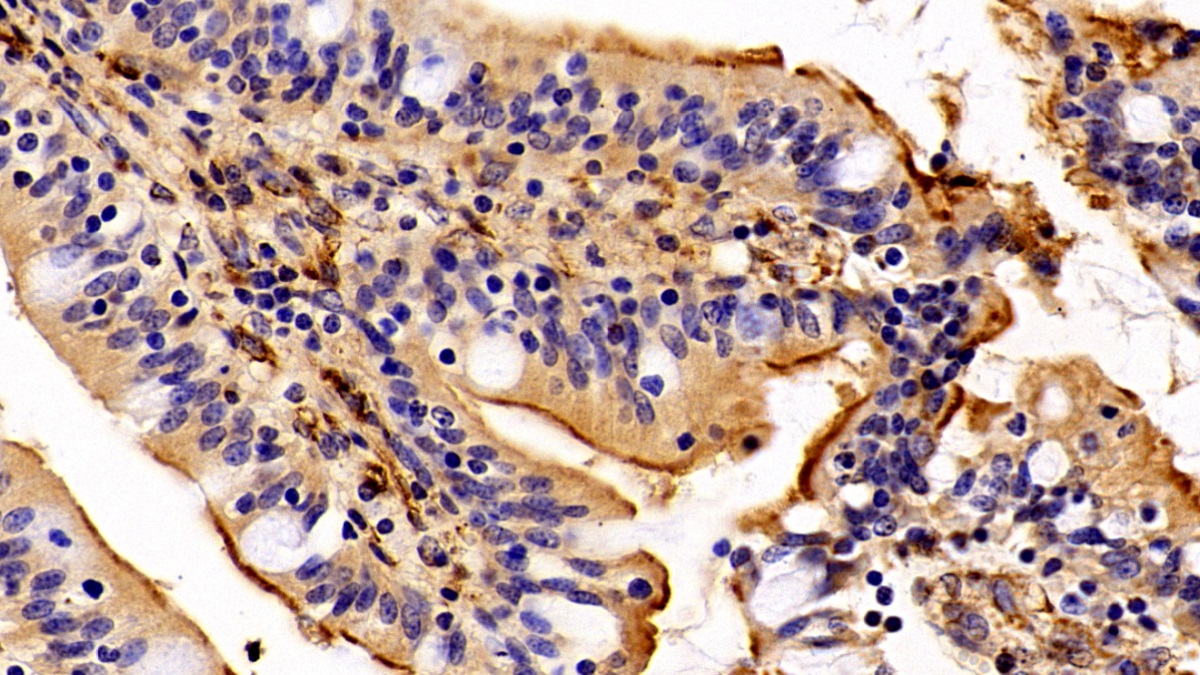

Использование высококачественных первичных антител является неотъемлемым условием получения точных и воспроизводимых результатов в современных научных исследованиях. Например, в рамках онкологического исследования удалось достоверно идентифицировать экспрессию белка PD-L1, что сыграло ключевую роль в оценке потенциальной эффективности иммунотерапии. Применение надежных антител обеспечило стабильность сигнала и высокую специфичность детекции, что позволило получить данные, пригодные для публикации в рецензируемых научных изданиях.